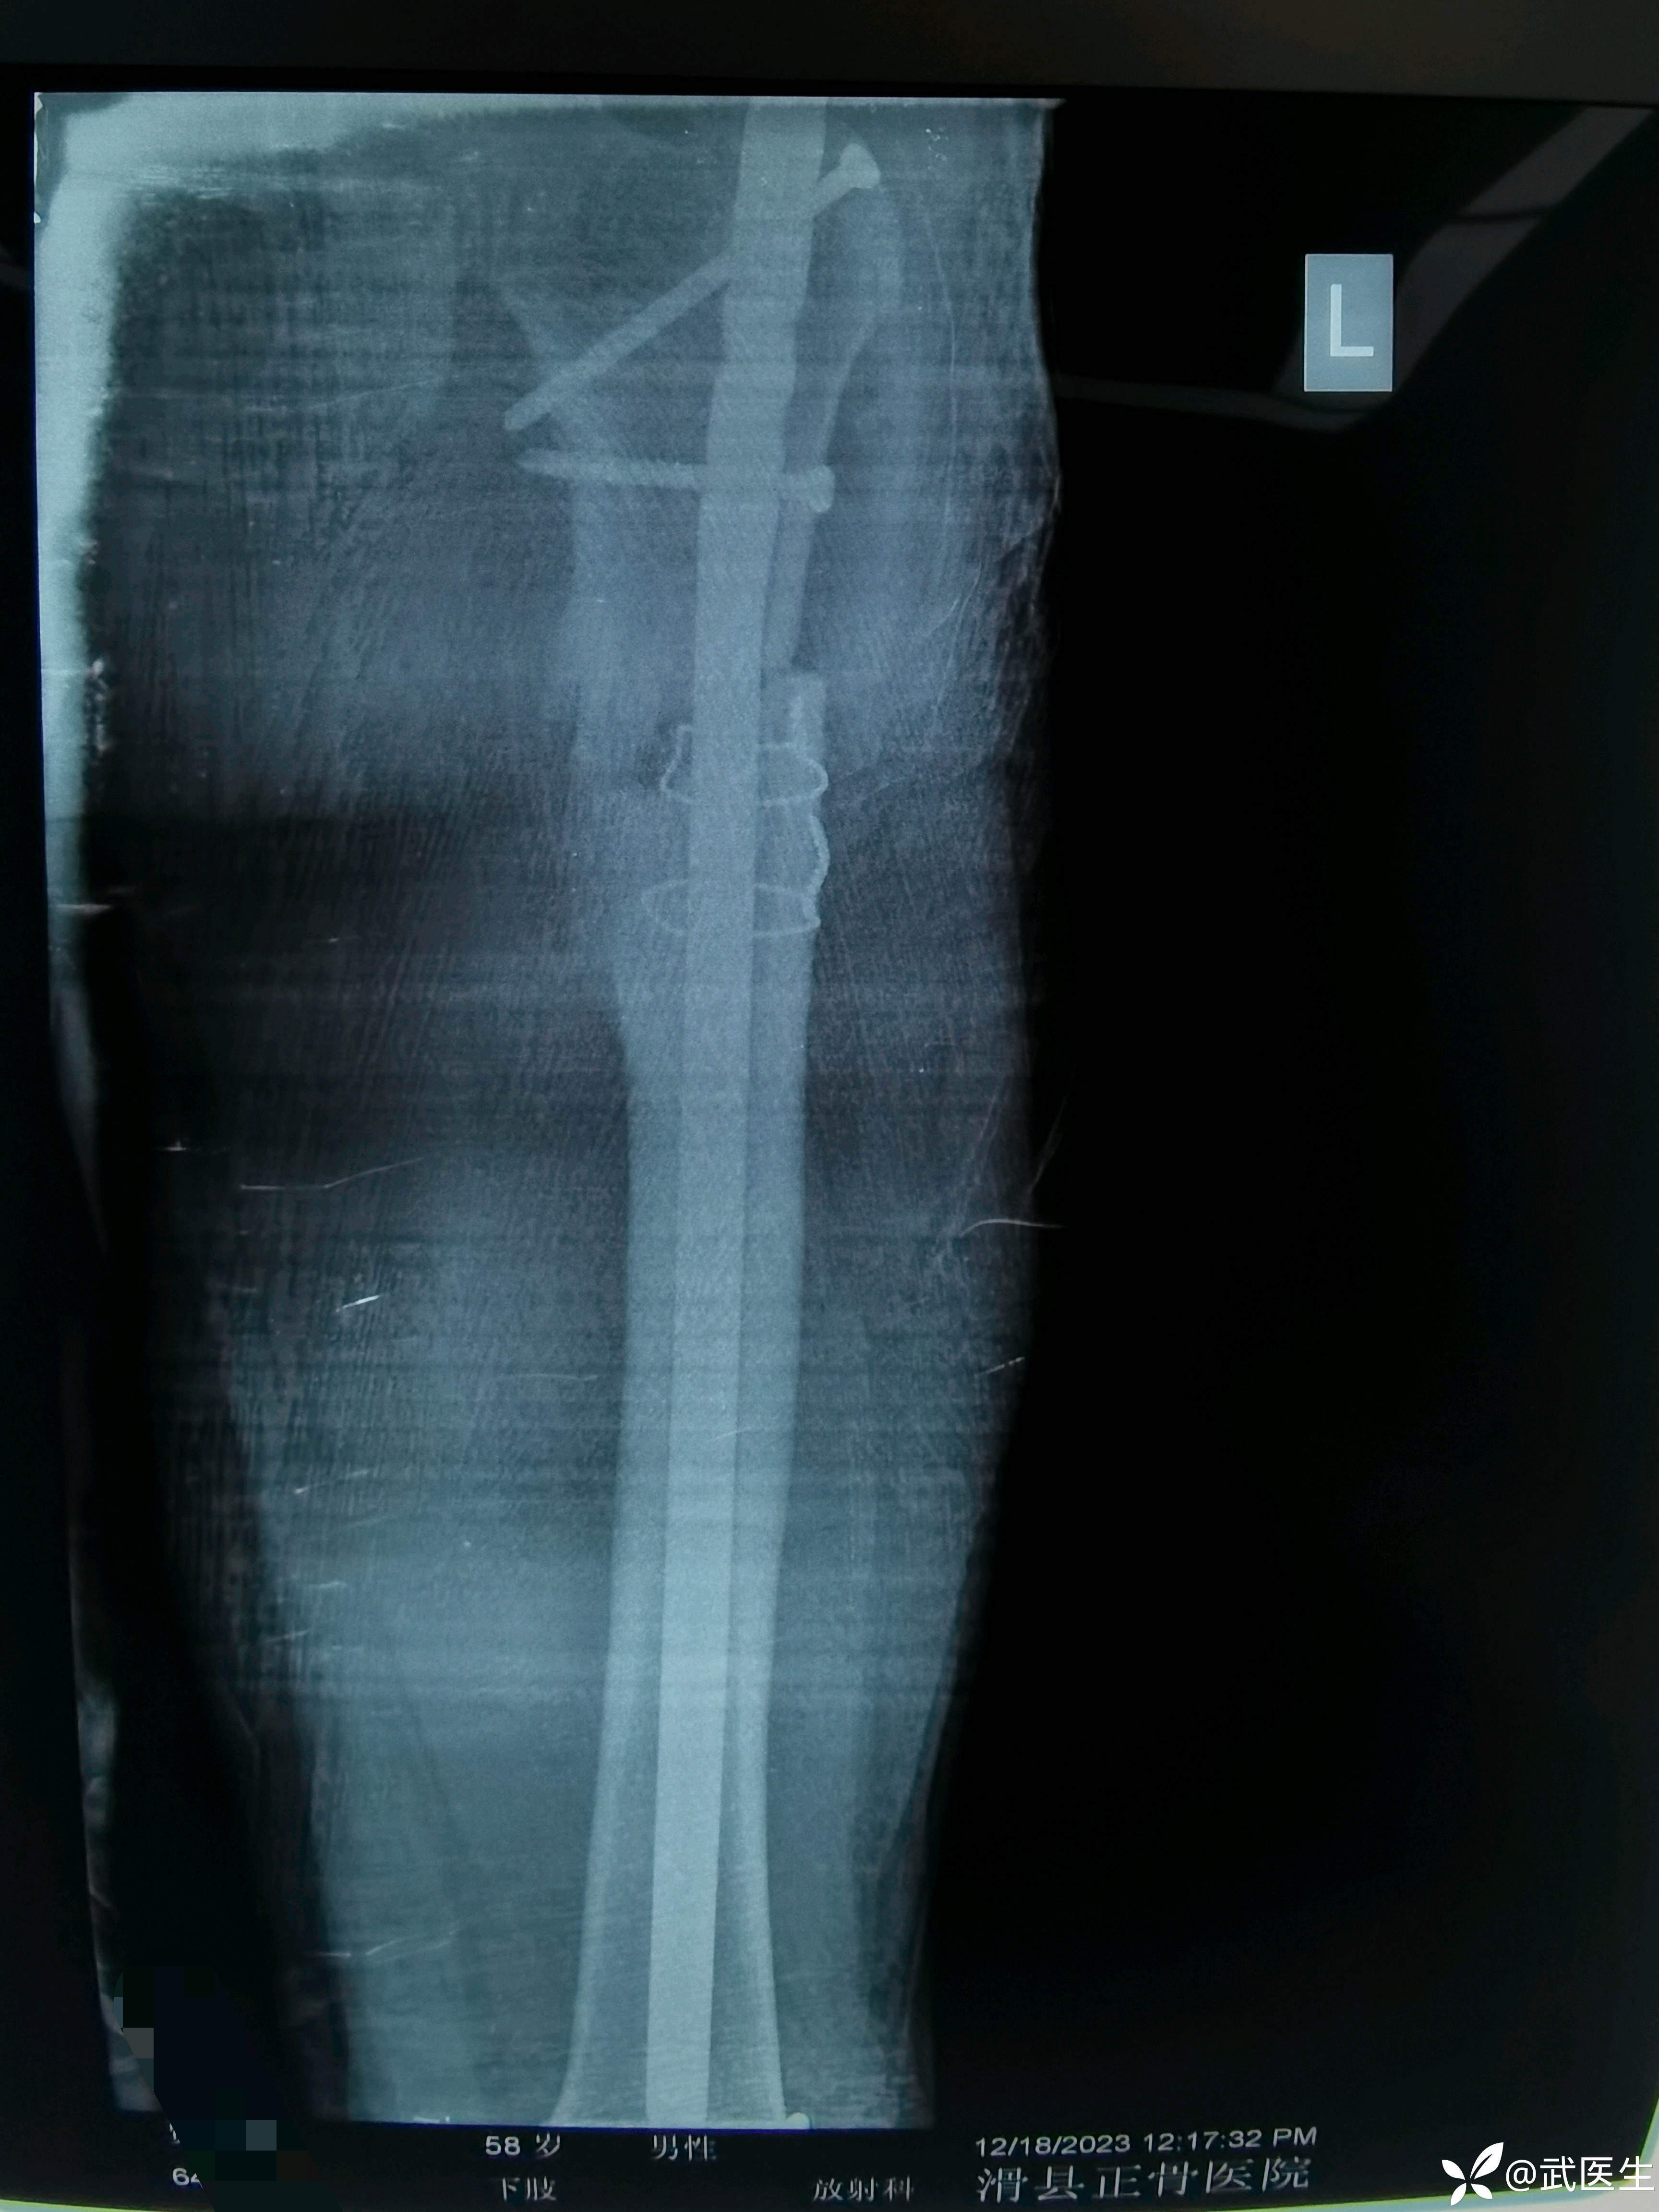

患者二十年前本院因股骨近端骨折手术治疗,于术后两年取出内固定,钢丝未取出。